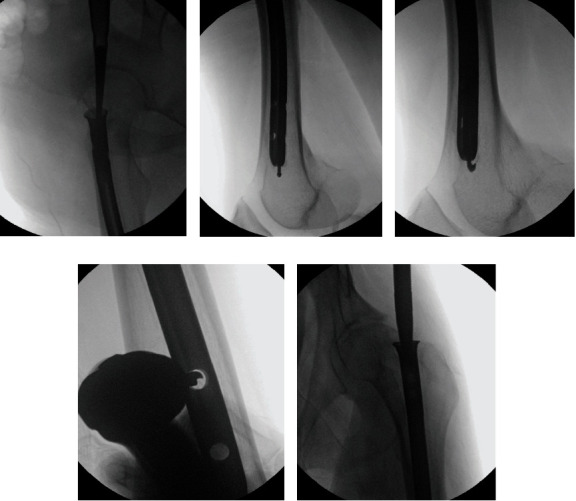

This paper presents a surgical technique for the removal of an old universal femoral nail preceding total hip arthroplasty (THA) in a 50-year-old male patient with left hip osteoarthritis. The patient had undergone femur nail insertion approximately 35 years ago. Due to the necessity of nail removal prior to THA, surgery to remove the nail was planned. There are challenges posed by the design of the old universal femoral nail system, particularly its side slot which made engagement of the conical bolt difficult. The successful removal of the nail was eventually achieved, enabling subsequent THA. Individuals who received this old implant years ago may now require its removal as part of osteoarthritis treatment. Given the lack of familiarity among surgeons with this outdated implant, this paper is aimed at providing essential guidance and insights regarding its removal procedure. This literature represents the inaugural documentation of the surgical technique for the removal of an aged femur nail.